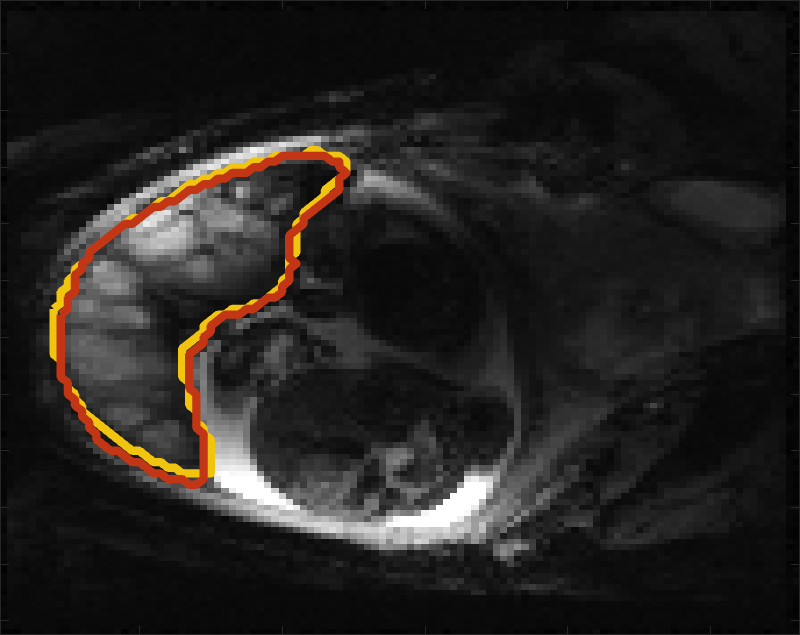

Despite its importance for many downstream clinical research tasks, placental segmentation is often performed manually and can take a significant amount of time, even for a trained expert. For BOLD MRI studies, manual segmentation is rendered more challenging due to the sheer number of MRI scans acquired and rapid signal changes due to the experimental design. Experiments acquire several hundred whole-uterus MRI scans to observe signal changes in three stages: i) normoxic (baseline), ii) hyperoxic, and iii) return to normoxic. During the hyperoxic stage, the BOLD signals increase rapidly, leading to hyperintensity throughout the placenta. Furthermore, the placental shape can undergo large deformation caused by maternal breathing, contractions, and fetal motion which can be particularly increased during hyperoxia [25]. See Fig. 1 for two examples.

Fig 3 compares the predicted label maps with ground truth on subjects with increasing Dice scores using the BW-CE model. The model accurately identifies the location of the placenta, but in the worst cases misses boundary details.